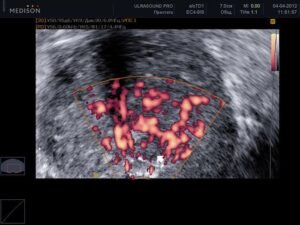

طریقہ کار سادہ ہے: اگر باقاعدہ صحت مند سرگرمیاں نہ ہوں تو نچلے جسم کے اعضاء میں خون کی گردش خراب ہوتی ہے، پیشاب کے مسائل شروع ہوتے ہیں، اور پروسٹیٹائٹس پیدا ہوتا ہے۔ ابتدائی مراحل میں اس مسئلے کی تشخیص مشکل ہوتی ہے، اور جب یہ سامنے آتا ہے تو اکثر جراحی مداخلت کی ضرورت پڑتی ہے۔ یورولوجی انسٹی ٹیوٹ سے لی گئی اس تصویر پر غور کریں:

48 سالہ مرد میں پروسٹیٹ کینسر۔ پروسٹیٹ کینسر صحت کی کمزوری سے دوچار مردوں میں موت کی سب سے بڑی وجہ (88% تک) ہے۔ یہ نچلے جسم کے اعضاء میں ناکافی خون کی گردش اور پروسٹیٹ میں سوزش کی وجہ سے ہوتا ہے۔ اس سے کینسر پیدا ہوتا ہے اور 1-2 سال کے اندر موت واقع ہو سکتی ہے۔